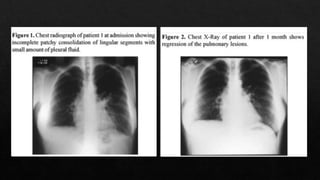

Un mes después

Es un Gramnegative, intracelular, obligado, que puede existir como un cuerpo reticular. Los organismos elementales, que son inactivos biologicamente y pueden sobrevivir en ambientes hostiles. La neumonía se desarrolla en 2 etapas: al inicio, los síntomas son similares a los de un resfriado (faringitis, laringitis, sinusitis), seguido de una neumonía moderada. La neumonía que dura entre 1 y 4 semanas es seguida por tos persistente que puede durar varias semanas.

Se estima quecausa 300,000 casos en EEUU cada año. Anti-C. pneumoniae anticuerpos son detectados en 50% de los individuos de 20 años. El porcentaje aumenta con la edad, teniendo un 70---80% en ancioanos. Tambien causa el 20% de las infecciones respiratorias bajas, y el 70% de los cuadros asintomaticos y leves, en los cuales se busca atencion medica. Un 3-10% de las neumonias adquiridas en la comunidad con causadas por este patogeno. En Latin America causa el 6% de estos cauadros, y es respondable del 20% de las einfecciones respiratorias altas Epidemiología